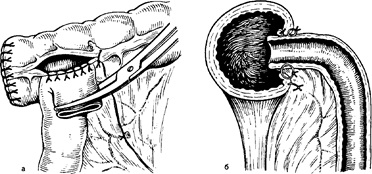

Ebben a műveletben, eltávolítjuk az egész jobb felét a vastagbél, befogják 10-15 cm-es szegmensét ileum végét, egy vak, felszálló vastagbél, a jobb oldali kanyar és jobb harmada a haránt vastagbélben (ábra. 11 a). Kerekítés a műveletet overlay sár-otransverzoanastomoza (ábra. 11, b, c).

Ábra. 11. Jobb oldali hemicolectomy (rendszer).

és - eltávolítását a határ b, c - ileotransverzoanastomozov típusok: 1 - alsó bryzheech Nye artéria; 2 - bal mintegy-zling artéria; 3 - szigmoid artéria; 4 - a felső pryamokischechnaya artéria; 5 - csípő vastagbél Arte-dence; 6 - A megfelelő kólika artéria; 7 - átlagos obodoch Nye artéria; 8 - superior mesenterialis artéria.